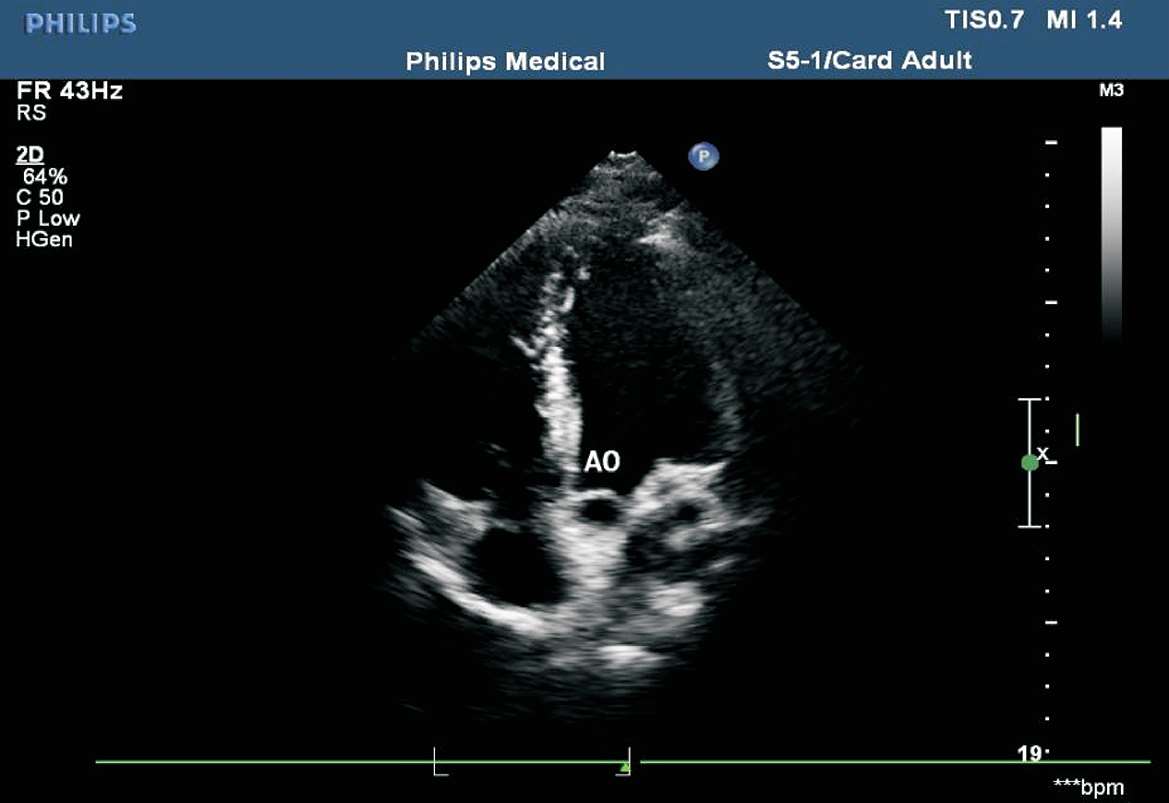

患者取平卧位或略向左倾斜,探头置于心尖搏动处,在心尖四腔心切面基础上稍向前上方倾斜。在此切面可了解主动脉瓣上血流速度、室间隔的完整性和左心室流出道有无病变(见图1-33)。

图1-33 心尖五腔心切面(AO:主动脉)